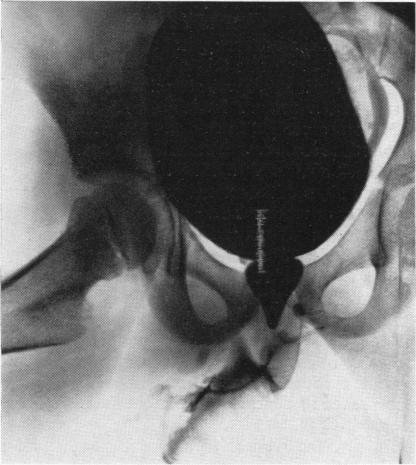

FISHER O D, FORSYTHE W I

Arch Dis Child. 1954 Oct;29(147):460-71. doi: 10.1136/adc.29.147.460.